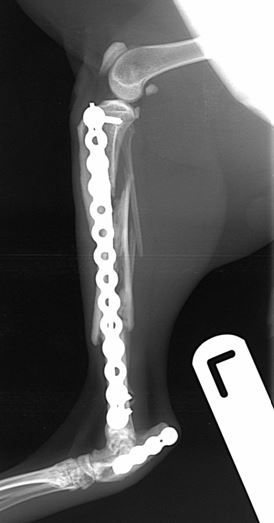

Fig. 1 A 6-year-old DSH cat with comminuted fractures of the tibia, fibula and calcaneus

Fig. 2 Immediate post-operative radiographs. A 2.4mm PAX plate with an intra-medullary pin has been used to repair the tibial fracture. A 2.0mm PAX plate has been used to repair the comminuted calcaneal fracture